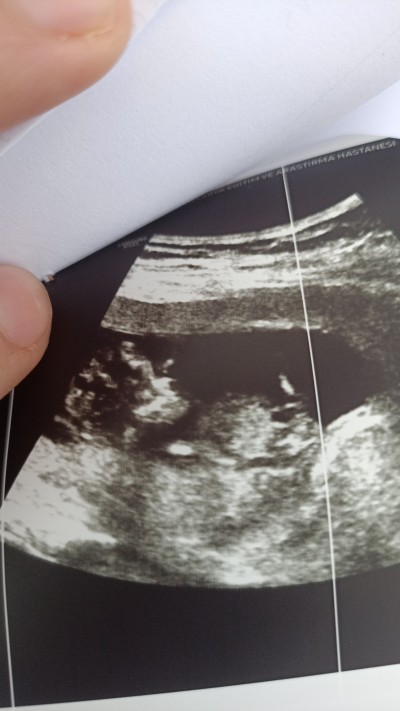

Cinsiyeti tahmini 🥺

Gebelik haftası 11

Kafa yapısı erkek gıbı duruyor canım

Cnm yüzde yüz erkek bence yinede hastaneye gidersen haber ver ben dün 20 haflaik hastaneye gitim kız ama seninki erkek diyorum